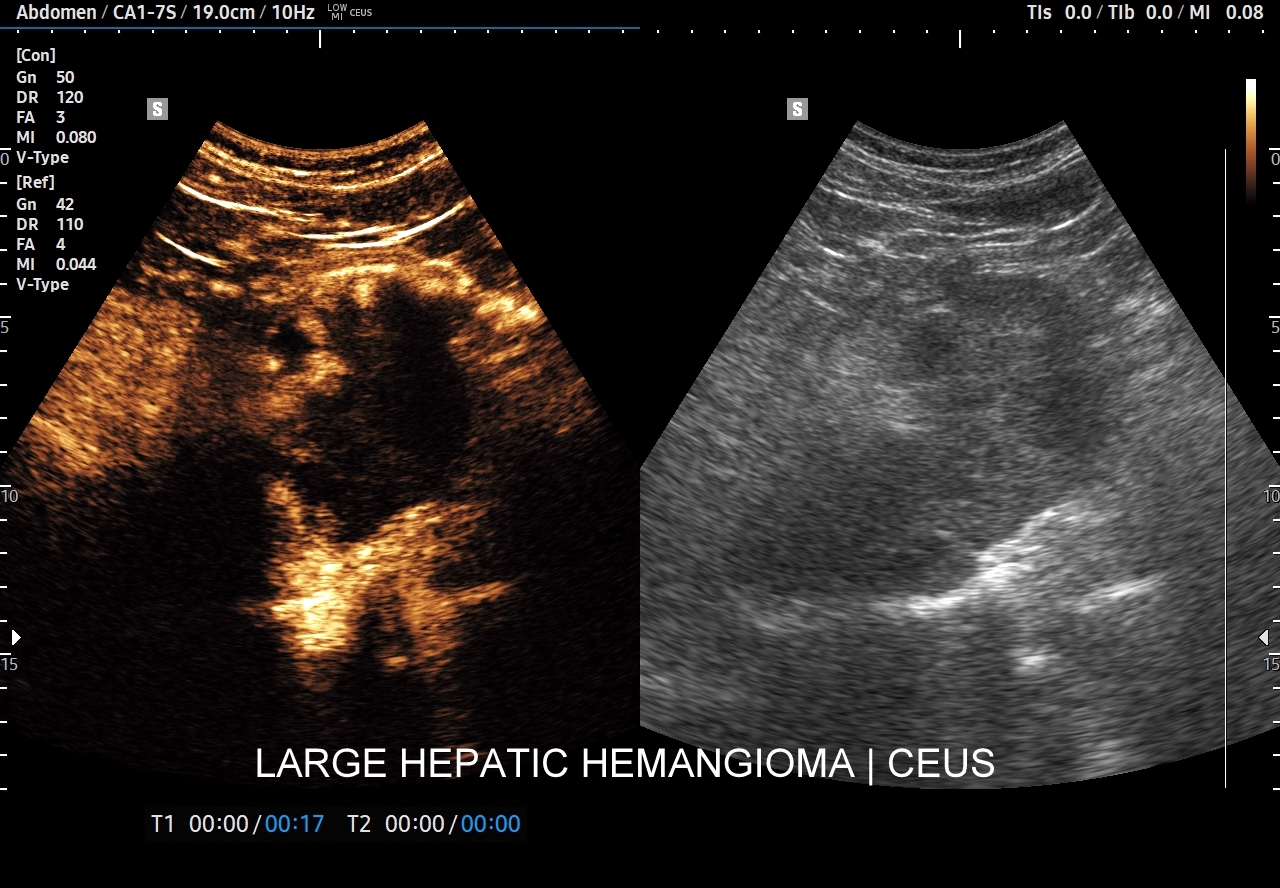

Najbardziej charakterystyczną cechą naczyniaka wątroby w badaniu CEUS jest jego wypełnianie w postaci guzkowej (ang. peripheral nodular enhancement) od obwodu ku centrum zmiany (ang. centripetal). Szybkość wypełniania bywa różnorodna, może być powolna lub szybka. W przypadku szybkiego wypełniania (tzw. flash-filling), w celu wykazania charakterystycznego centrypetalnego wypełniania niezbędna może być postprocessing’owa analiza poklatkowa zapisanego nagrania badania. W fazie późnej naczyniak wątroby pozostaje izowzmocniony lub hyperwzmocniony w stosunku do natywnego miąższu wątroby.

W przypadku dużych naczyniaków obszary, które uległy wykrzepianiu pozostają awaskularne przez wszystkie fazy badania CEUS, tj. nie wypełniają się kontrastem (nonenhancing). W przeciwieństwie do powyższego konstelacja, w której to w fazie wczesnej pojawia się wzmocnienie, a następnie w fazie wrotnej lub późnej ulega wypłukaniu (hypoenhancement) świadczy o cechach złośliwych diagnozowanej zmiany ogniskowej w wątrobie i wyklucza rozpoznanie naczyniaka.